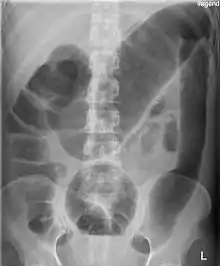

مگاکولون توکسیک

مگاکولون توکسیک ( megacolon toxicum ) یک نوع انبساط حاد کولون است. [1] علائم این بیماری شامل انبساط شکمی، تب، شکم درد، شوک می شود.

مگاکولون توکسیک معمولاً عارضه ای از بیماری های التهابی روده ای مانند کولیت زخمی و به ندرت بیماری کرون و بعضی از عفونت های روده بزرگ، از جمله عفونت های کلستریدیوم دیفیسیل است که منجر به کولیت پسودوممبران می شود، است. نوع دیگری از مگاکولون وجود دارد و می تواند مادرزادی باشد (از زمان تولد، مانند بیماری هیرشپرونگ ). همچنین می تواند توسط شیگلا و انتاموبا هیستولیتیکا ایجاد شود. همچنین ممکن است توسط استفاده از داروی لوپرامید ایجاد شود .